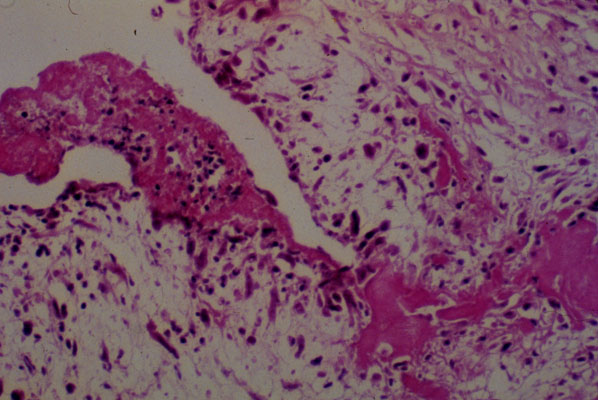

Rheumatic endocarditis, histology

Rheumatic endocarditis early stage, histology. The fibrin aggregate on the surface of the valve is attached to the valve by ingrown granulation tissue. The valve is edematous and contains an increased number of fibroblasts and vessels admixed to chronic inflammatory cells.